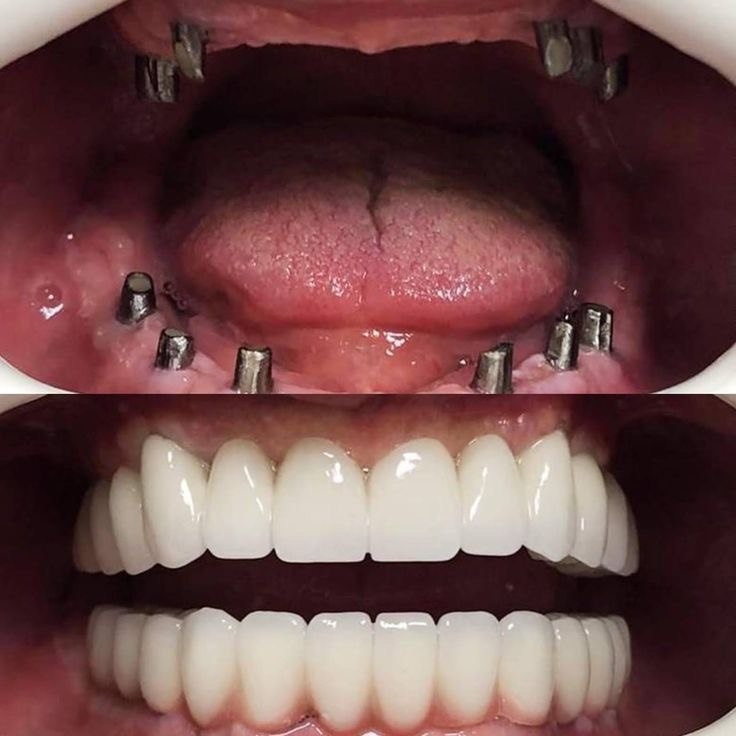

Стоматология «5 Принципов» в Симферополе гордится своими достижениями в области имплантации и постоянного совершенствования качества обслуживания. Наши клиенты получают индивидуально подобранные решения, основанные на передовых технологиях, годах опыта и внимании к деталям. Мы предлагаем комплексный подход: от подробной консультации до восстановления жевательной функции и эстетики улыбки.Каждый этап начинается с точной диагностики: цифровая томография, планирование в 3D, моделирование улыбки. Это позволяет увидеть предполагаемые результаты до начала операции и минимизировать риски.

При имплантации мы используем современные системы имплантатов с высоким процентом приживления и минимальным временем восстановления. Наши специалисты владеют техниками одномоментной фиксации и протезирования без необходимости временной съемной конструкции, что обеспечивает быструю адаптацию и комфорт пациента.В портфолио клиники — примеры успешных восстановлений: имплантация одиночного зуба с естественным оттенком коронки, комплексная реконструкция зубного ряда, а также имплантация с последующим использованием циркониевой коронки для максимальной эстетики. Мы уделяем внимание функциональности, долговечности и гармонии с природной линией улыбки.Послеоперационное сопровождение — важная часть our подхода: контроль за имплантатами, профилактические процедуры и рекомендации по уходу. В «5 Принципы» мы стремимся вернуть уверенность и комфорт улыбке каждого клиента в Симферополе.